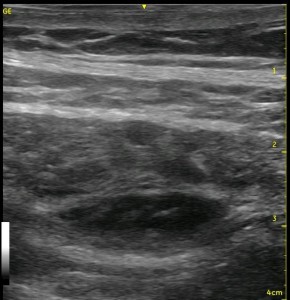

I think I felt it! Was that a ‘pop’? I slowed my needle speed a little just then, and I’m not sure if that was a ‘pop’ or not. Hmmm…pushing harder is just tenting the muscle downward. Maybe I’m through. Oh yea, I’m using ultrasound. I’ll just inject a cc or 2 and see if I’m in the right place or not! OK, they injected too slow. I didn’t see that very well. Let’s try again. Nope, I am definitely still in the bottom of the Internal Oblique, and this is going to be a pretty long incision, so it HAS to be within the plane! I’ll advance some more. Definitely a ‘pop’ that time! Oh, well, now I’m a little too far into the Transversus Abdominus muscle by the look of that injection. I’ll back up some and inject I guess. Now…well, it sort of looks right. There is swelling sort of around the place where there used to be a clear thick white line. Now that clear thick white line is gnarled and sort of everywhere, and it isn’t obvious that the local is spreading above or below or within the Transversus Abdominus Plane. Of course, this would also be the injection where we accidentally get air in the image as well, further obscuring my view!

Sometimes, you can’t get the needle right where you want it, or a few confirmatory injections of local anesthetic distorts the local ‘architecture’ of the tissue. If you have done lots of TAP blocks, this has happened to you without question! You start with an awesome image, and end up with something like the image below.

Look at the images below. They appear to be a series of pictures arranged from the beginning of an injection to the end. In fact, no further injection is added. The first image is taken at the periphery of a TAP block, and the subsequent images are taken as the probe is slid closer to the center of the injection. They confirm that the needle is adequately placed within the appropriate plane though the central position is a bit difficult to interpret.